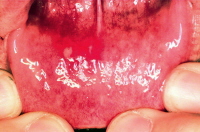

Một hội chứng có thể nhận ra một cách rõ ràng là đặc trưng bởi các tổn thương dạng mụn nước trên miệng và ban đỏ trên tay chân và đôi khi cả vùng mông. Kèm theo sốt. Tổn thương da điển hình là các đỏ dịch bao quanh bởi vùng đỏ halo (elliptical vesicle surrounded by an erythematous halo) theo hình ảnh tổn thương trình bày trong bài.

Về tác nhân gây bệnh, bệnh tay chân miệng do siêu vi trùng đường ruột thuộc nhóm Coxasackieviruses và Enterovirus 71 gây ra. Bệnh lây lan nhanh qua các chất tiết từ mũi, miệng, nước bọt khi trẻ ho, hắt hơi bắn ra hoặc dính từ tay trẻ bệnh sang trẻ lành. Biểu hiện bệnh thường cho thấy trẻ bị lở, loét niêm mạc miệng, chảy nước bọt nhiều. Các nốt lở loét có đường kính 2-3mm, xuất hiện ở vòm họng, phía trong má, lợi, lưỡi. Bệnh khiến trẻ chán ăn hoặc bỏ ăn, quấy khóc, khó ngủ, hay giật mình, trẻ có thể không sốt , sốt nhẹ hoặc sốt cao. Một số trẻ mắc bệnh tay chân miệng không điển hình sẽ không có tất cả các triệu chứng nêu trên mà chỉ loét miệng, bóng nước không rõ ràng mà chỉ có chấm hoặc ban màu hồng.